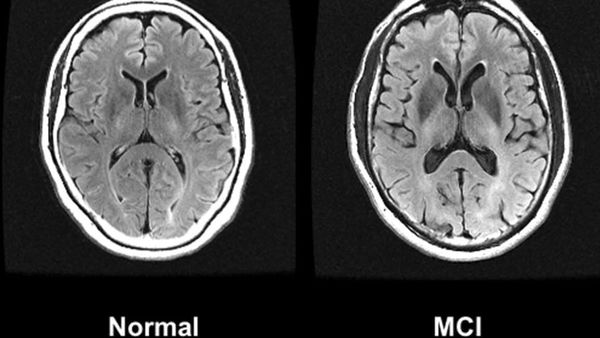

New Alzheimer’s drug rejected by NICE Despite setbacks, the quest for groundbreaking Alzheimer’s treatments continue.